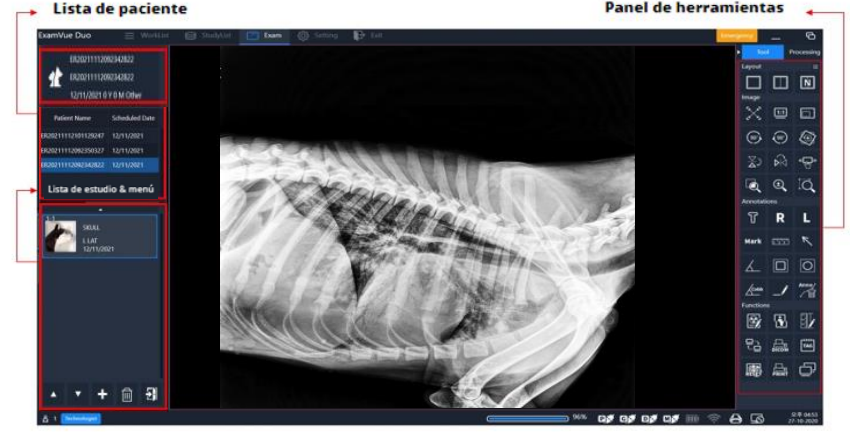

MANUAL DE USUARIO EXAMVUE DUO VET